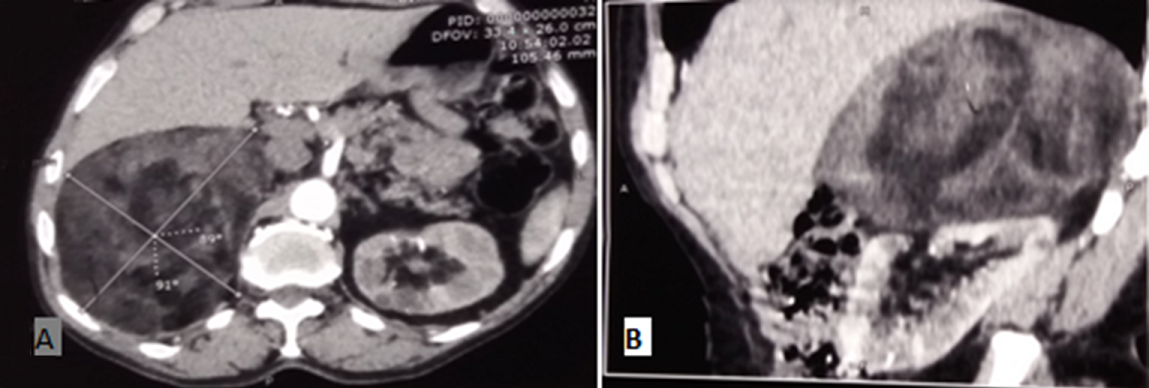

Le myélolipome surrénalien est une tumeur rare, bénigne, non sécrétante, souvent de découverte fortuite. Sa physiopathologie serait une métaplasie des cellules de la corticosurrénale en cellules réticulo-endothéliales en réponse à une infection, à un stress chronique ou à une dégénérescence de la surrénale. La moyenne d’âge de découverte est vers la cinquantaine. Histologiquement, la tumeur est constituée de tissu graisseux mâture, associé à du tissu hématopoïétique normal. Ainsi l'échogénicité de la tumeur est fonction de la prédominance de la composante graisseuse ou myéloïde. Son diagnostique est porté par le scanner qui identifie le contingent graisseux. Toutefois, ces aspects radiologiques peuvent prêter à confusion avec l'angiomyolipome du rein, le lipome et le liposarcome d'où l’intérêt de l'IRM. Habituellement respecté, l'exérèse du myélolipome est indiquée quand il est volumineux, compressif ou présentant un risque hémorragique. Nous rapportons le cas du patient AL A, 75 ans, hospitalisé pour masse surrénalienne, révélée par des lombalgies droites, irradiant vers l'hypocondre droit, sans signes d'hypersécrétion endocrine. L'examen clinique a révélé une sensibilité de la fosse lombaire droite. Le bilan de phéochromocytome et de corticosurrénalome s'est révélé sans anomalies, notamment les dérivés méthoxylés urinaires de 24heures et le freinage minute. Le patient a été opéré par cœlioscopie, avec à l'examen anatomo-pathologique un aspect de myélolipome surrénalien.